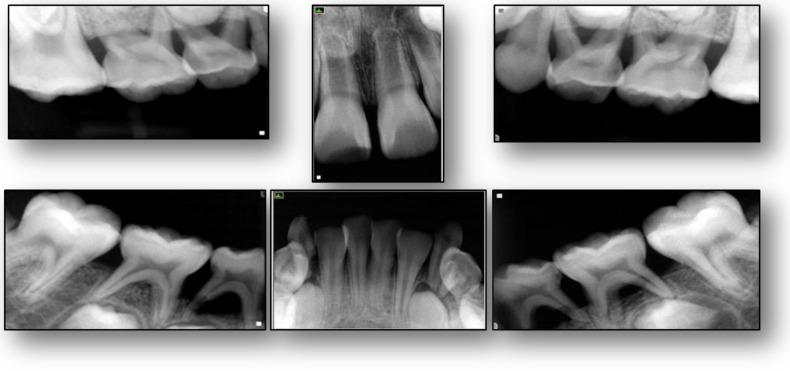

: Glycogen storage diseases (GSDs) are genetic disorders that result from defects in the processing of glycogen synthesis or breakdown within muscles, liver, and other cell types. It also manifests with impaired neutrophil chemotaxis and neutropenic episodes which results in severe destruction of the supporting dental tissues, namely the periodontium. Although GSD Type Ib cannot be cured, associated symptoms and debilitating oral manifestations of the disease can be managed through collaborative medical and dental care where early detection and intervention is of key importance. This objective of the case report was to describe a child with GSD Ib and its associated oral manifestations with microbial, immunological and histological appearances. : An eight-year-old Hispanic male with a history of GSD type Ib presented with extensive intraoral generalized inflammation of the gingiva, ulcerations and bleeding, and intraoral radiographic evidence of bone loss. was readily identifiable from the biofilm samples. Peripheral blood neutrophils were isolated and a deficient host response was observed by impaired neutrophil migration. Histological evaluation of the soft and hard tissues of the periodontally affected primary teeth showed unaffected dentin and cementum. : This case illustrates the association between GSD Ib and oral manifestations of the disease. A multi-disciplinary treatment approach was developed in order to establish healthy intraoral conditions for the patient. Review of the literature identified several cases describing GSD and its clinical and radiographic oral manifestations; however, none was identified where also microbial, immunological, and histological appearances were described.

糖原贮积病(GSDs)是一种遗传性疾病,由肌肉、肝脏和其他细胞类型内糖原合成或分解过程中的缺陷引起。它还表现为中性粒细胞趋化性受损和中性粒细胞减少发作,这会导致支持性牙齿组织即牙周组织的严重破坏。虽然Ib型糖原贮积病无法治愈,但通过协作的医疗和牙科护理可以控制该疾病的相关症状和使人衰弱的口腔表现,其中早期发现和干预至关重要。本病例报告的目的是描述一名患有Ib型糖原贮积病的儿童及其相关的口腔表现,包括微生物学、免疫学和组织学表现。:一名有Ib型糖原贮积病病史的8岁西班牙裔男性,出现广泛的口腔内牙龈广泛性炎症、溃疡和出血,以及口腔内骨质流失的影像学证据。从生物膜样本中很容易识别出来。分离外周血中性粒细胞,观察到中性粒细胞迁移受损导致宿主反应不足。对受牙周影响的乳牙的软组织和硬组织进行组织学评估,显示牙本质和牙骨质未受影响。:本病例说明了Ib型糖原贮积病与该疾病口腔表现之间的关联。为该患者制定了多学科治疗方法,以建立健康的口腔内环境。文献回顾发现了几例描述糖原贮积病及其临床和影像学口腔表现的病例;然而,未发现同时描述微生物学、免疫学和组织学表现的病例。